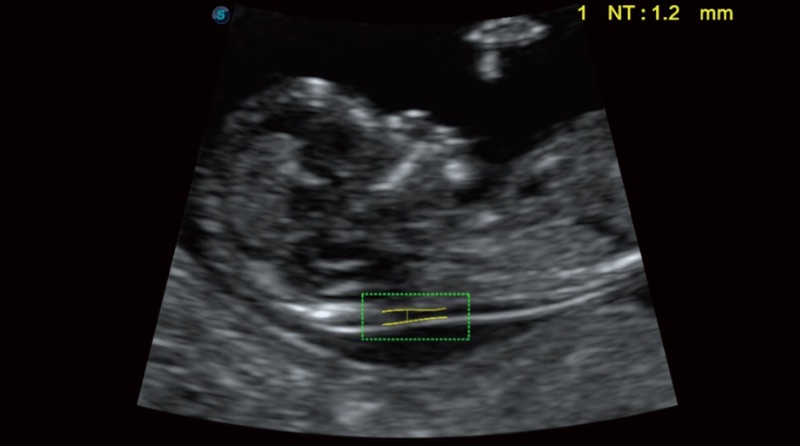

Auto NT ermöglicht halbautomatische, standardisierte Messungen der Nackentransparenzdicke in 2D-Bildern und verringert die Abhängigkeit des Anwenders von den Ergebnissen.